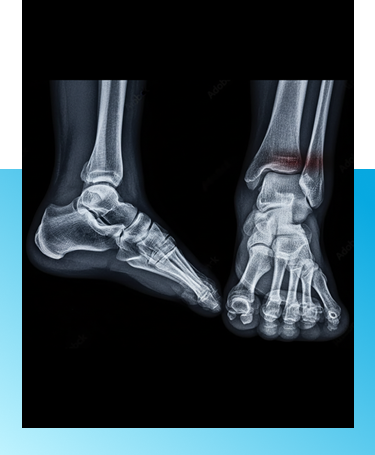

Ankle Fracture Treatment in Port Washington, New York

At Northern Ankle Foot Associates, we provide comprehensive evaluation and personalized care for ankle fractures in Port Washington, focused on stabilizing injury and preserving long term function.

Ankle fracture treatment in Manhasset, NY

Ankle fractures commonly result from falls, sports injuries, twisting accidents, or direct impact. Depending on the severity, the fracture may be stable or require more advanced intervention. Prompt evaluation is essential to ensure proper alignment and prevent long-term instability or arthritis. If you experience sudden ankle pain, swelling, or difficulty bearing weight, immediate assessment is recommended.